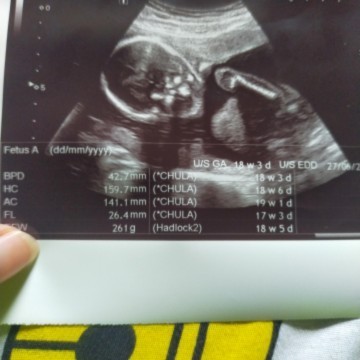

น้องคลอดก่อนกำหนดตอน 32 วีค ตอนคลอดก็น้ำหนักตัวแค่ 1,440 กรัม ตอนนี้อายุ 3 เดือน 5 วันแล้ว ยังไม่อ้อแอ้ ไม่ยิ้มเลย เวลาเรียกก็ไม่หันตามเสียง ร้องไห้งอแง จะกินนมอย่างเดียว ไม่ตื่นมาเล่นเลย น้องจะปกติไหมค่ะ ลูกใครเป็นแบบนี้บ้าง #ท้องแรกคะ #ขอบคุณสำหรับคำตอบค่ะ #ขอคำแนะนำหน่อยค่ะ #ขอบคุณล่วงหน้านะคะ #ใครมีประสบการณ์